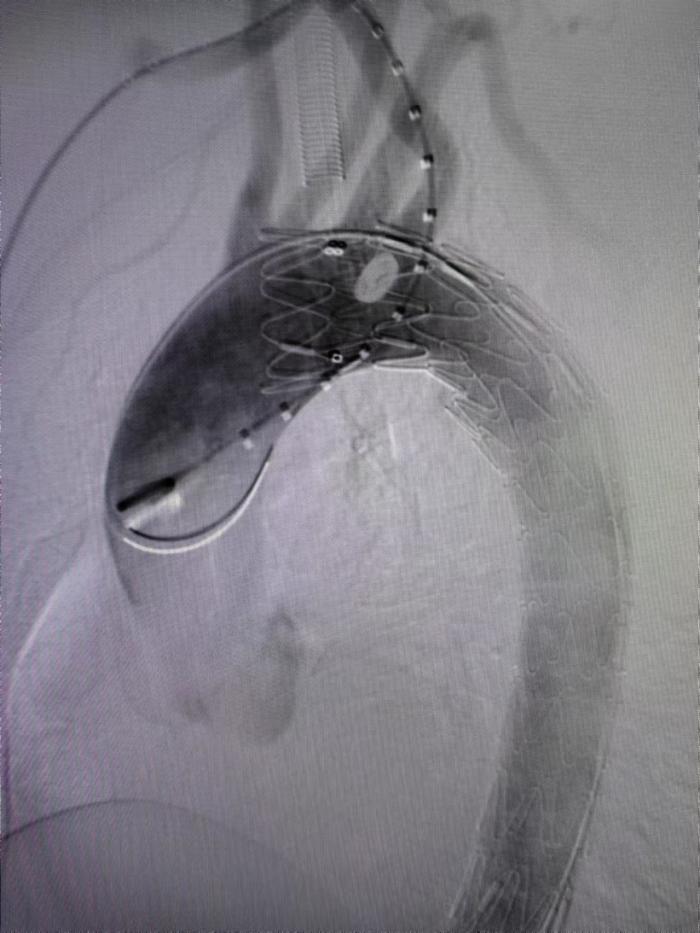

1月24日,湘南学院附属医院介入血管外科主任周定中手术团队,在一个小小支架上打开两扇小小窗户,成功为一名复杂主动脉综合征(主动脉壁间血肿、穿透性溃疡)伴先天性血管变异(迷走右锁骨下动脉)患者实施主动脉“双开窗”支架植入术,在完整封闭主动脉病变区的同时,保住了支架覆盖区域所有重要分支动脉,重建主动脉生命通道。

依据术前CTA测量动脉长度、直径、角度、距离及开口位置,术中造影再次确认,治疗团队根据所测数据先对支架进行“双开窗”改装,在支架上裁剪出与对应的左、右锁骨下动脉出口等圆的两个小洞。开弓没有回头箭,支架上的“窗户口子”一旦打开就无法复原。最终,医务人员凭借精确测量和娴熟手法攻克了这个难关,成功完成体外“双开窗”手术。最后在主动脉造影下精准定位血管位置,成功释放支架,顺利实现了病变区完全隔绝,所有分支完整保留。